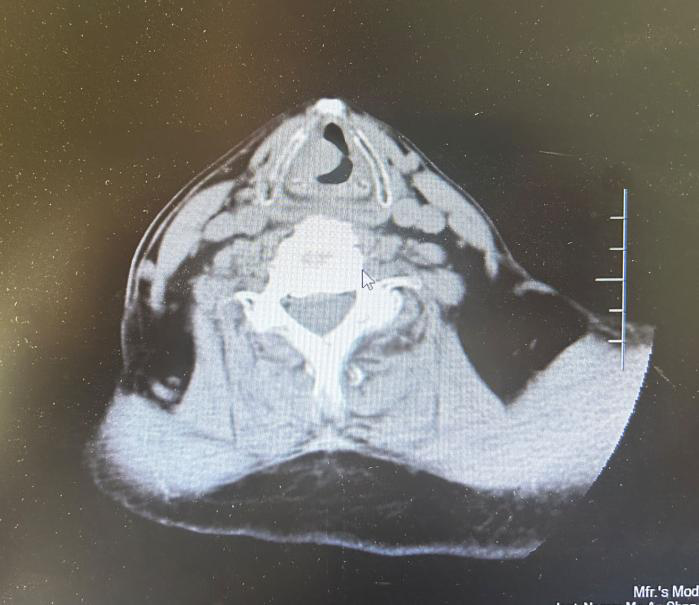

CT示:右側(cè)聲帶占位性病變,聲門旁間隙消失。